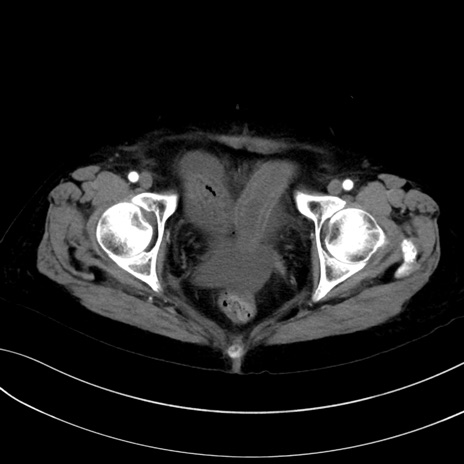

症例13 CT(横断像)1日半後